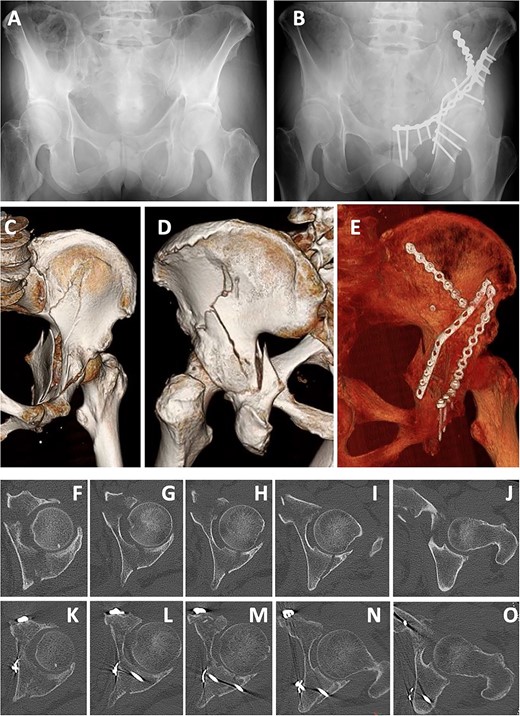

A 66-year-old man, who walked with a stick, was injured in a fall during a sudden convulsion. He could not move his left lower extremity due to pain and rested in his house. After 3 days, he developed a fever (>38°C) and was admitted to a nearby hospital. Diagnostic imaging showed a quadrilateral fracture (Fig. 7A, B, D, E). Twelve days after injury, open reduction and internal fixation for the acetabular fracture were performed using a low-profile pelvic plate system by the classical ilioinguinal approach, as in case 1. After a 13-hole reconstruction plate was bent and placed at the quadrilateral surface, screws were inserted to the posterior column and ischium using the sleeve guide technique (Fig. 7C, F–I). Six weeks after the operation, partial weight-bearing was started. After 3 months, he was able to walk with a rollator, and after 1 year, he walked with a stick.

Case 2 images: (A) pre-operative X-ray, (B) pre-operative axial CT image, (C) post-operative X-ray, (D) pre-operative 3D-CT, (E) pre-operative coronal CT image, (F) post-operative 3D-CT, (G–I) post-operative axial CT images. Screws are inserted into the posterior wall (G, H) and near the ischial tuberosity (I).